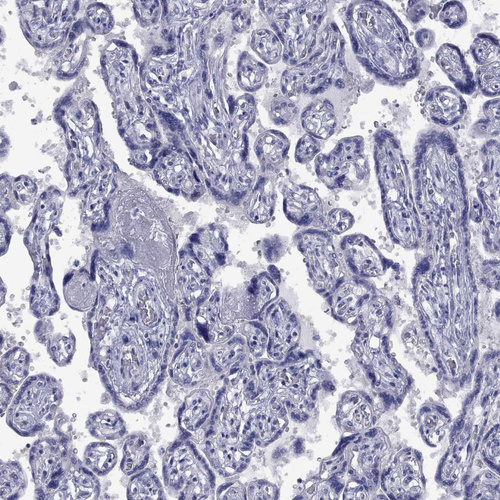

Immunohistochemical staining of human liver shows weak to moderate membranous positivity in bile duct cells.